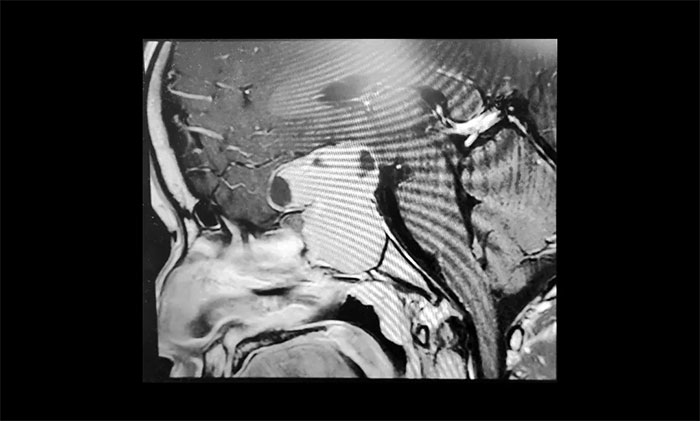

▲ 术前影像:巨大垂体瘤,向鞍上生长

为了进一步确定瘤体的位置和大小,当即进行了鞍区MRI平扫+增强。影像显示,蝶鞍显著扩大,鞍区见一“塔样”肿块灶,病变总矢横高径约3.5×4.5×5cm。瘤体向鞍上生长,占据鞍上池,明显推移视交叉、分界模糊,三脑室前下部受压变形。鞍底塌陷、蝶窦填充;侵及包绕两侧海绵窦约1/2,海绵窦向外侧移位。

结合影像检查,潘仁龙主任、李士其教授会诊后一致达成共识。由于巨大垂体瘤长期压迫视神经,患者视物出现异常,右眼已经失明,手术指征明显,应尽快手术,尽可能挽救患者视力。